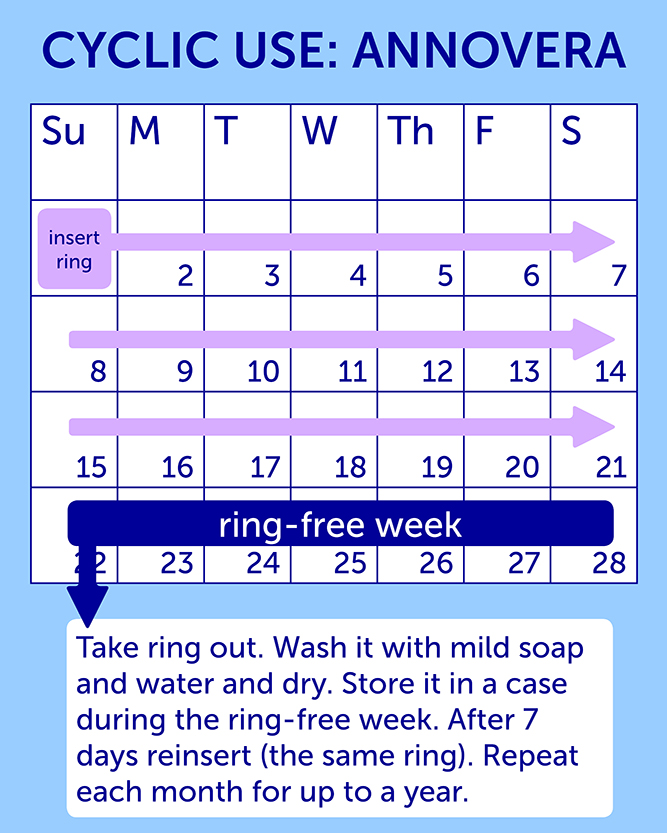

Annovera Ring Side Effects. After the 7 days are up insert Annovera again for the next 21 days and continue this process for up to 12 months. Nausea vomiting diarrhea stomach pain. If experienced these tend to have a Less Severe expression i. Headachemigraine nauseavomiting vaginal yeast infection candidiasis lowerupper abdominal pain painful periods vaginal discharge urinary tract infection breast paintenderness irregular vaginal bleeding diarrhea and genital itching.

Headache Nausea Breast tenderness Yeast infections Irregular bleeding Abdominal pain Genital itching During studies comparing the pill patch and ring researchers found that women who used the ring had more genital irritation and vaginal discharge than women who used the pill. Headache including migraine nauseavomiting vaginal yeast infection candidiasis lowerupper abdomen pain painful periods vaginal discharge urinary tract infection breast paintenderness irregular vaginal bleeding diarrhea genital itching USE ANNOVERA is a ring-shaped vaginal system with. Each of these side effects was experienced by fewer than 2 of the women participating. Call your doctor for medical advice about side effects. Get emergency medical help if you have signs of an allergic reaction. During the 7 days its removed youll get your period.

During a clinical trial of more than 2000 women using Annovera the side effects that caused women to stop using Annovera included irregular bleeding headaches vaginal discharge vaginal infections and nausea. Youd still need to remember to take out Annovera after 3 weeks of keeping it in place and then reinsert it after 1 week. Some less serious side effects include. ANNOVERA does not protect against HIV infection AIDS and other sexually transmitted infections. Allergic reactions such as skin rash or itching hives swelling of the lips mouth tongue or throat.

During the 7 days its removed youll get your period. NuvaRings possible risks include. Headaches nausea abdominal pain increased period pain. Call your doctor for medical advice about side effects. Its not listed on the brands list of side effects so I thought Id see if this has ever happened to other women or if I need to see a doctor.

After the 7 days are up insert Annovera again for the next 21 days and continue this process for up to 12 months. Is anyone here on the Annovera ring. Uses How to use Side Effects Reviews Uncontrolled high blood pressure Heart problems Diabetes Increased risk of blood clots Undiagnosed abnormal uterine bleeding Potential hepatitis C drug combinations containing ombitasvir paritaprevir or ritonavir with or without. Annovera has similar side effects to the pill and NuvaRing because they use the same kind of hormones. Headachemigraine nauseavomiting vaginal yeast infection candidiasis lowerupper abdominal pain painful periods vaginal discharge urinary tract infection breast paintenderness irregular vaginal bleeding diarrhea and genital itching.

Headaches nausea abdominal pain increased period pain. Some less serious side effects include. Pain or burning when you urinate. Its not listed on the brands list of side effects so I thought Id see if this has ever happened to other women or if I need to see a doctor. Youd still need to remember to take out Annovera after 3 weeks of keeping it in place and then reinsert it after 1 week.